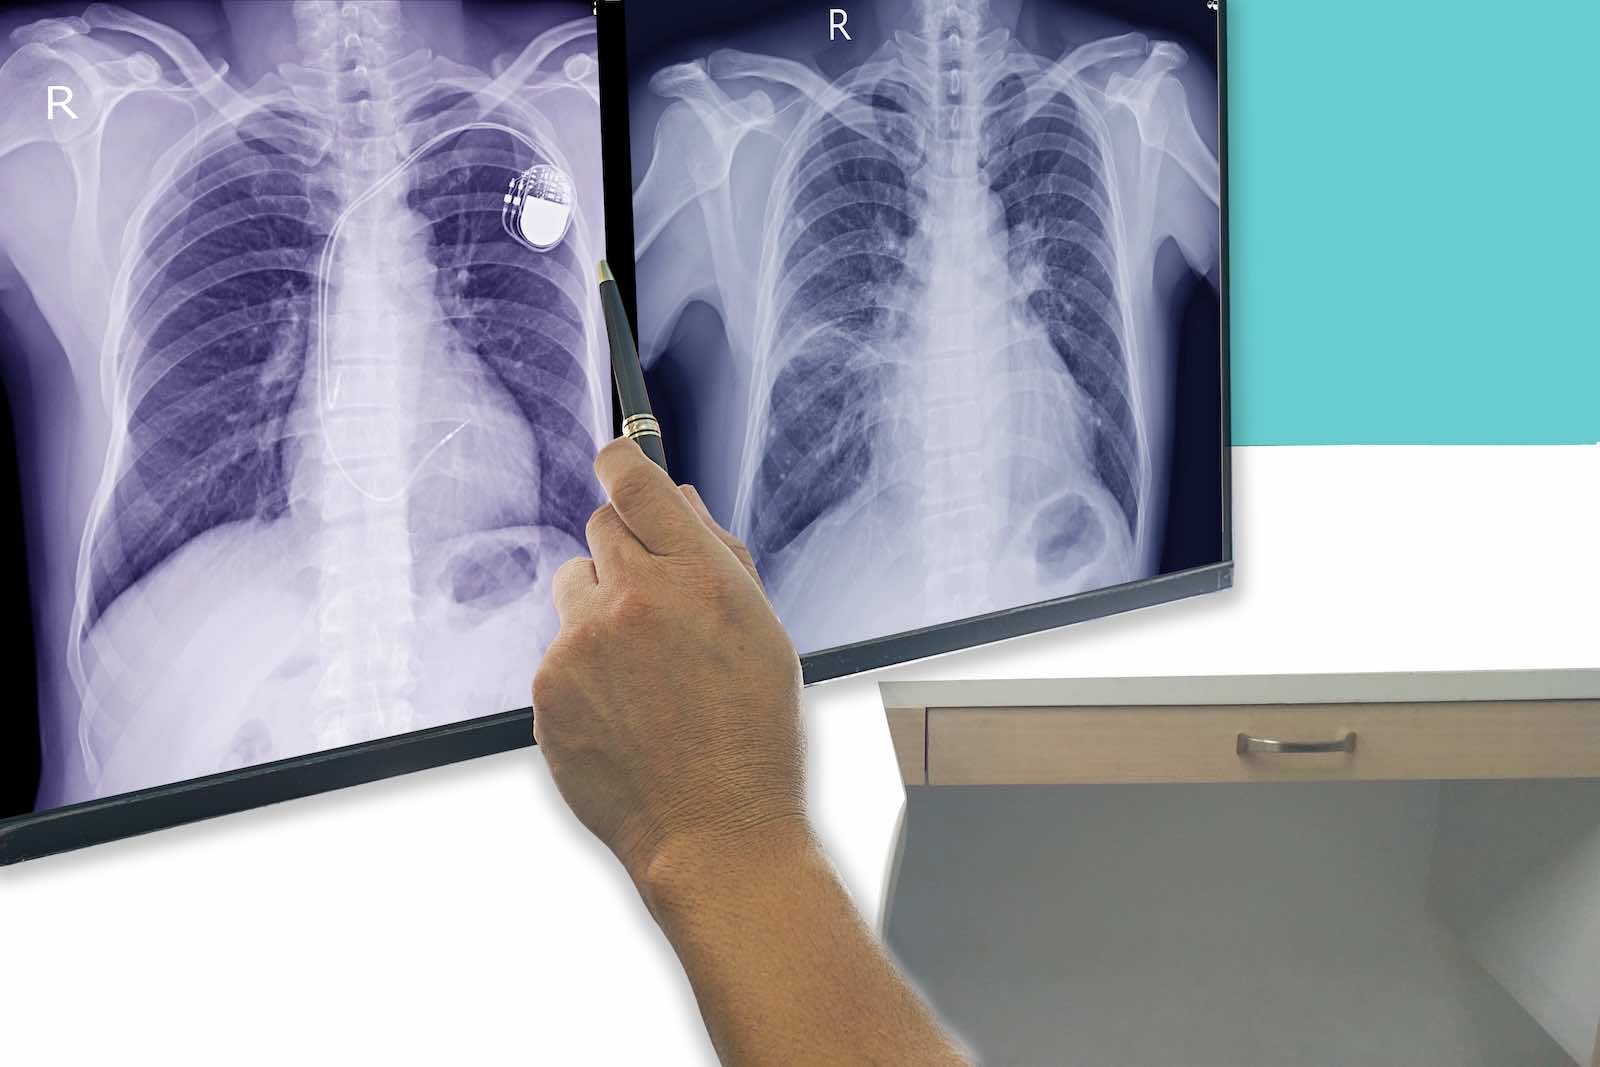

Die Kardiologie ist die Lehre vom Herzen und seinen Erkrankungen. Bei KardioPro bieten wir eine umfassende Bandbreite an diagnostischen Verfahren, um die Funktion und Struktur Ihres Herzens präzise zu beurteilen. Dazu gehören unter anderem das Ruhe- und Belastungs-EKG, der Langzeit-EKG zur Detektion von Herzrhythmusstörungen, sowie der Herzultraschall (Echokardiographie) zur Beurteilung der Herzklappen und der Pumpleistung.